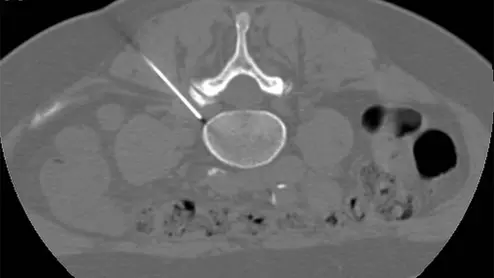

pulsed radiofrequency for sciatica

In PRF procedures, a probe is used to intermittently apply energy directly to the dorsal root ganglia, which is often where pain and neurologic symptoms associated with sciatica originate.